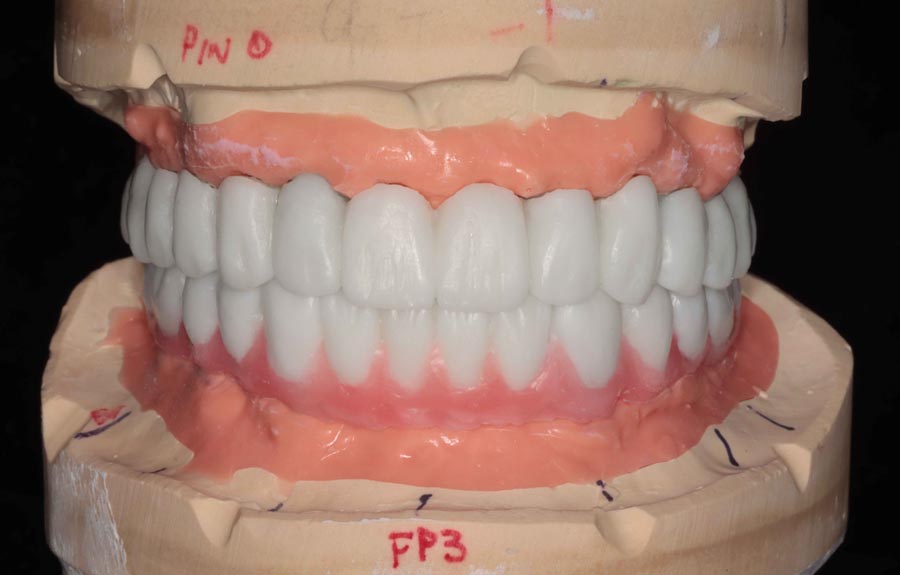

Prototype wax-up, frontal. Any imperfections or patient requests are changed in this prototype stage.